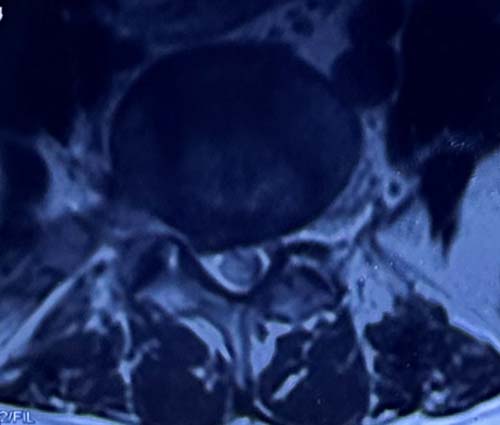

患者小张腰痛伴左下肢小腿外侧疼痛麻木4年,严重影响生活,慕名到省立医院脊柱外科崔新刚教授处就诊,崔新刚教授仔细检查后确诊为腰椎间盘突出症,需要手术治疗。

针对患者年纪轻需要尽量保留活动节段的情况,崔新刚教授确定为患者实施OBE内镜下髓核摘除术,去除椎间盘突出髓核解除疼痛。同时,因患者体重较大,髓核摘除术后突出复发风险要高于其他人。崔新刚教授决定在OBE内镜下髓核摘除后行纤维环缝合术,降低患者术后复发风险。仅用时不足1小时,崔新刚教授顺利完成OBE髓核摘除术+纤维环缝合术。术后患者疼痛解除。